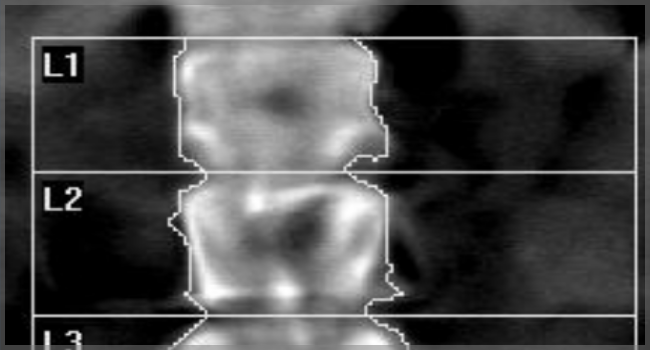

BoneStation - Reporting for Bone Densitometry

BoneStation is an enterprise class, web-based software solution for DXA-based bone densitometry. BoneStation streamlines workflow for bone density practices and simplifies the interpretation of bone density scans for reading physicians/radiologists.

BoneStation was initially developed as a custom application for a major teaching hospital. After a successful deployment, Cardea commercialized BoneStation. Today, BoneStation is used at hospitals in the U.S. and Europe.